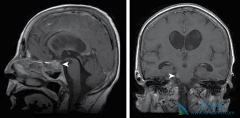

• 什么是肺癌脑转移以及肺癌脑转移症状有哪些

什么是肺癌脑转移以及肺癌脑转移症状有哪些

什么是肺癌脑转移?脑转移瘤系指原发于身体其他部位的肿瘤细胞转入颅内,其发病率占颅内肿瘤的3.5%-10%,目前以 肺癌脑转移 最多见。非小细胞肺癌在作出诊断时约有20%的患者已有脑转移,而非小细胞肺癌患者在病程中约有30%左右发生脑转移,其中以大细胞 ...

• 不同组织类型的患者肺癌脑转移能活多久有差异

不同组织类型的患者肺癌脑转移能活多久有差异

肺癌发展到了晚期,经常会出现转移,根据转移的不同部位,会产生不同的症状,而超过一半的肺癌可能出现脑转移,那么,出现 肺癌脑转移能活多久 ?肺癌脑转移患者预后差,自然平均生存时间仅 1~2 个月。专家表示,肺癌脑转移是晚期肺癌较常出现的现象。 ...